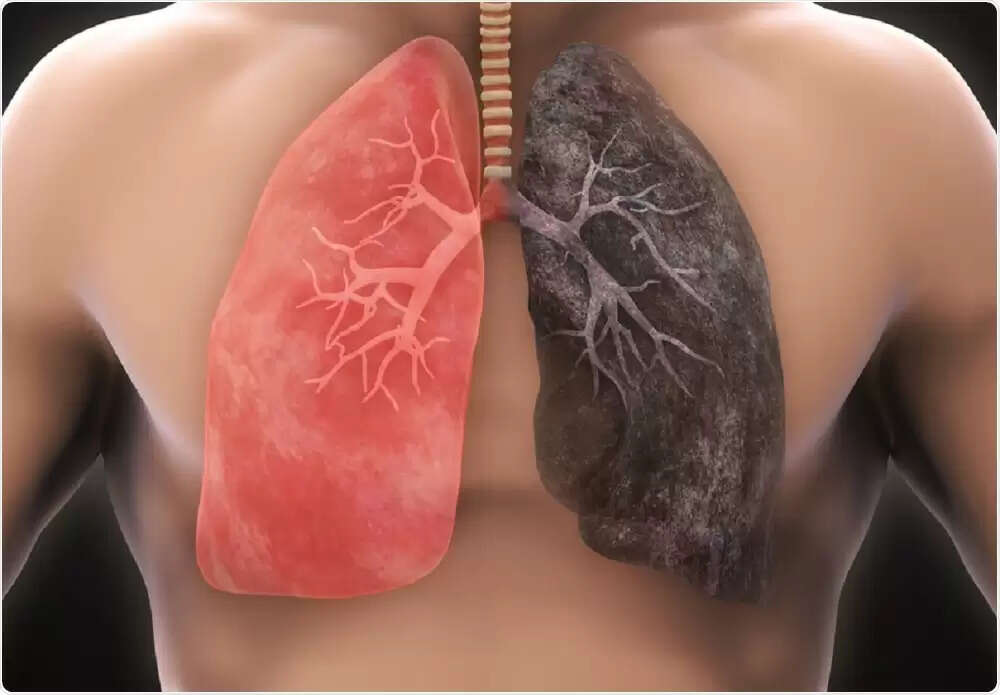

எந்த ஜென்மத்திலும் கேன்சர் வராமலிருக்க எந்தெந்த உணவுகளை ஒதுக்க கூடாது தெரியுமா ?

தற்போது அனைத்திலும் ரசாயனங்கள் பயன்படுத்தப்படுகின்றன. விவசாய பொருட்கள் முதல் பால் கொடுக்கும் பசு வரை அனைத்திலும் ரசாயனம் இருப்பதால் அதை வாங்கி சாப்பிடும் நாம் அதன் மூலம் புற்று நோய் தாக்குதலுக்கு ஆளாகிறோம்

புற்றுநோயைத் தவிர்க்க என்ன சாப்பிட வேண்டும்?